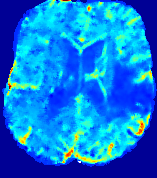

4.3.2 Diffusion Imaging via Advection-Diffusion

Slice #1Slice #2Slice #3Slice #4Slice #5Slice #6Dgtsuperscript𝐷gtD^{\text{gt}}Refer to captionRefer to captionRefer to captionRefer to captionRefer to captionRefer to captionDestsuperscript𝐷estD^{\text{est}}Refer to captionRefer to captionRefer to captionRefer to captionRefer to captionRefer to captionRefer to caption0.300.300.300.240.240.240.180.180.180.120.120.120.060.060.060.000.000.00(mm2/s)𝑚superscript𝑚2𝑠(mm^{2}/s)𝐕est𝟐subscriptnormsuperscript𝐕est2\|\bf{V}^{\text{est}}\|_{2}Refer to captionRefer to captionRefer to captionRefer to captionRefer to captionRefer to captionRefer to caption0.00300.00300.00300.00240.00240.00240.00180.00180.00180.00120.00120.00120.00060.00060.00060.00000.00000.0000(mm/s)𝑚𝑚𝑠(mm/s)

Figure 15: PIANO identifiability testing: diffusion imaging via advection-diffusion. Top row shows Dgtsuperscript𝐷gtD^{\text{gt}} used for simulating ground truth pure diffusion. Rows below show the estimated Destsuperscript𝐷estD^{\text{est}} and 𝐕est2subscriptnormsuperscript𝐕est2\|{\bf{V}}^{\text{est}}\|_{2} on corresponding slices. Note that the plotted value scale for 𝐕est2subscriptnormsuperscript𝐕est2\|{\bf{V}}^{\text{est}}\|_{2} is 0.01 of that for Dgtsuperscript𝐷gtD^{\text{gt}} and Destsuperscript𝐷estD^{\text{est}}.

Similarly, we test the behavior of PIANO when estimating both advection and diffusion from a pure diffusion-driven process. The goal is to determine if PIANO is able to recognize that there is only diffusion governing the given concentration time-series. We use the same ‘Diffusion Imaging’ data simulation of Sec. 4.2.1 as the concentration dataset, PIANO estimates both velocity 𝐕estsuperscript𝐕est{\bf{V}}^{\text{est}} and diffusivity Destsuperscript𝐷estD^{\text{est}}. Estimation results in Fig. 15 confirm PIANO’s identifiability again: the estimated 𝐕est2subscriptnormsuperscript𝐕est2\|{\bf{V}}^{\text{est}}\|_{2} is almost invisible compared to Destsuperscript𝐷estD^{\text{est}}, even plotted with a 1%percent11\% value range compared to that for Destsuperscript𝐷estD^{\text{est}}. On the other hand, Destsuperscript𝐷estD^{\text{est}} achieves comparable estimation performance as ‘Diffusion Imaging via Diffusion’ in which PIANO predicts Destsuperscript𝐷estD^{\text{est}} alone (shown in Fig. 13).